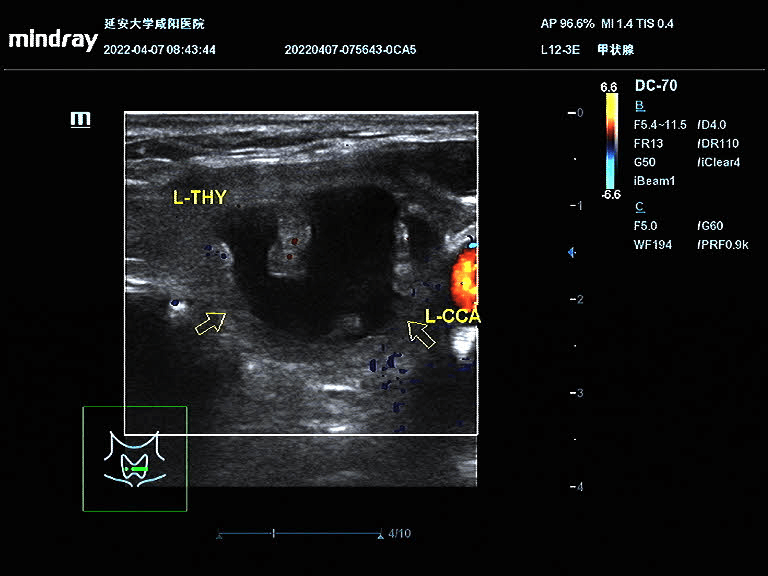

王女士在半年前因頸部包塊就診于我院,超聲提示甲狀腺左葉囊實性包塊,因疫情原因未進一步治療;近半年來包塊明顯增大,頸部膨隆,為進一步治療就診于我院血液內(nèi)分泌科。彩超診斷為甲狀腺左側(cè)葉囊實性結(jié)節(jié),患者因懼怕疼痛,不愿手術(shù),選擇保守治療;后得知甲狀腺結(jié)節(jié)可以超聲引導(dǎo)下微創(chuàng)治療,遂聯(lián)系超聲科進行咨詢;超聲科醫(yī)生對王女士的甲狀腺結(jié)節(jié)進行評估后,就射頻消融術(shù)的優(yōu)點、術(shù)前的準備、術(shù)中的風(fēng)險、術(shù)后的注意事項詳細講解,王女士當即決定選擇射頻消融術(shù)治療甲狀腺結(jié)節(jié)。4月9日下午在介入超聲手術(shù)室順利完成手術(shù),術(shù)后頸部僅一個針眼大小。術(shù)中囊性部分抽吸為黑紅色粘稠液,實性部分消融治療,術(shù)后即刻造影結(jié)節(jié)內(nèi)未見造影劑回聲。

術(shù)前結(jié)節(jié)大?。?4.9mm×31.8mm×22.2mm